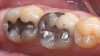

4. Bond/Seal Maintenance Risk Assessment

Figure 4  Image of preparation with poor substrate and subgingival margins where maintaining seal would be difficult. High-strength ceramics or metal ceramics would be indicated.

Figure 4